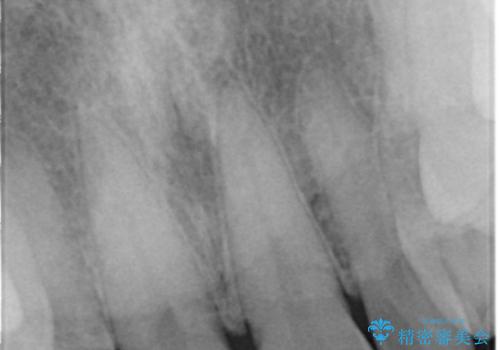

- 上の前歯の一部が欠けてしまったので治療を希望し来院された患者様です。

破折状態から歯髄(歯の神経)は保存できると判断し、クラウンでの治療を計画しました。